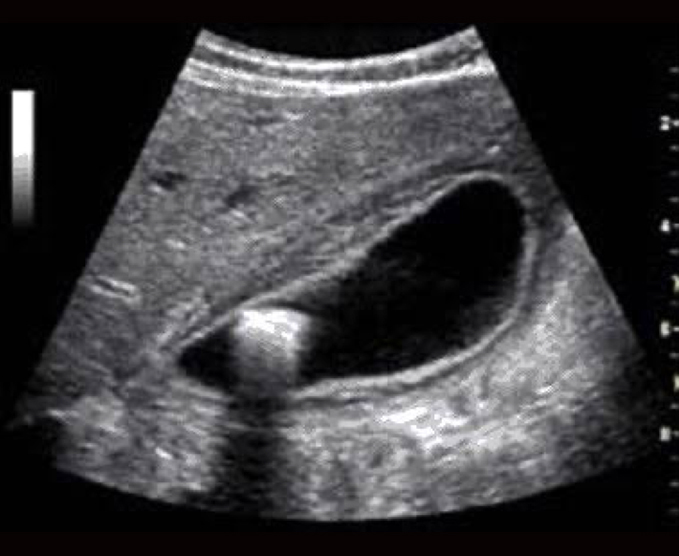

Es una prueba diagnóstica que utiliza ondas sonoras de alta frecuencia que hacen contacto con los órganos y que son convertidas automáticamente en imágenes de la zona explorada.

Normalmente se realiza a través de la piel, aplicando un gel acuoso que sirve de contacto a un dispositivo llamado transductor, el cual se mueve por la zona a explorar mientras el médico radiólogo puede observar en tiempo real las imágenes que se generan en el monitor del ecógrafo.

- Ultrasonido pélvico

- Ultrasonido renal

- Ultrasonido hepatobiliar

- Ultrasonido de abdomen